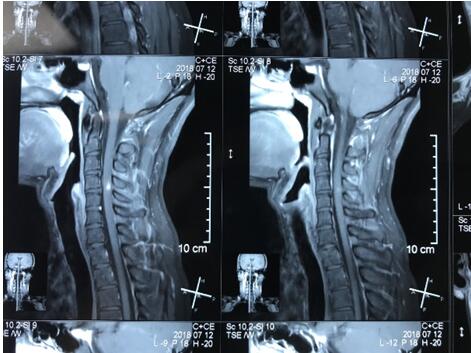

小张开始意识到自己情况的严重性,在家人的陪同下前往当地医院就诊。颈椎核磁共振显示,小张脊髓里有个异常信号,但不能明确诊断出这个异常信号究竟是什么疾病的表现。为寻找确切的治疗,小张辗转多家医院,结果仍然是不能明确这个信号代表的是何种疾病,陆陆续续的治疗也没有起到任何好转的效果。为了查明病因,小张慕名找到了我院神经内一科主任王展航。

作为广东省知名的神经内科专家,王展航对小张的病情非常重视,多次亲自对患者进行精细的神经专科查体。结合患者既往胃病史及外院核磁共振片显示的脊髓后索病灶,他提出“脊髓亚急性联合变性”的诊断意见, 并制定了详细的治疗计划。仅仅用药一周,小张就觉得肢体的麻木感有所缓解.病情明显好转后出院。

院长助理兼神经内一科科主任王展航指出,脊髓亚急性联合变性是由于维生素B12缺乏导致的神经变性疾病,累及脊髓后索、侧索白质及周围神经,常表现为下肢深感觉障碍,周围神经病变,感觉性共济失调等。其中,深感觉障碍所致的走路踩棉花感常常是这个病的典型特点。维生素B12在神经髓鞘的合成中起重要作用,缺乏或吸收不良后会使神经髓鞘出现退行性变化。除了维生素B12外,内因子因素,如抗内因子抗体、先天内因子缺乏、胃病及营养不良都可能引起该病。